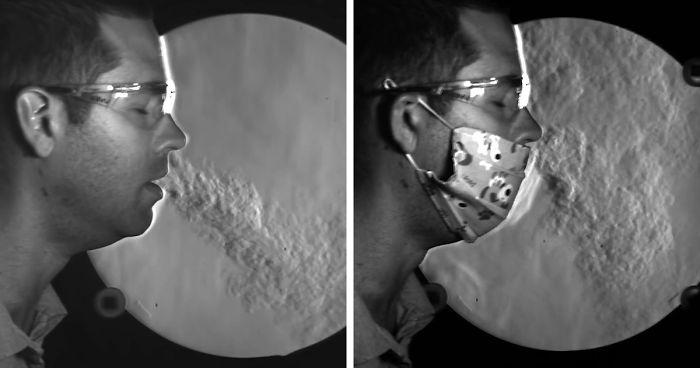

Видео показва как различните маски пречат на разпространението на COVID-19

Д-р Джо Хансън от YouTube каналa It's Okay To Be Smart създаде това страхотно видео, което показва защо трябва да продължим да носим тези защитни средства. Той се позовава на едно от последните изследвания по темата.